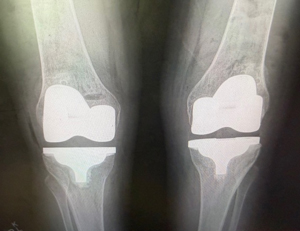

Lynnie After XR

I can't believe the picture of my legs before and after…I was so relieved to get back to Calgary and not have to think about planes and cars and hotels and reservations. You were the most relaxing part of this whole adventure. Honestly, I felt soooooo cared for and in such capable hands and I was sooo out of it….I didn't even dream. It just all happened. And you and Angie and your dream team, I’m soooo grateful. United Airlines lost my walker..…but we eventually made it safely here to an empty quiet comfortable home in Calgary… and slept… and thus my legs and body have stopped spasming, but I will go get muscle relaxers if they start again. Right now, all I have to do is ice and rest and marvel at my legs as I walk to the bathroom. My left leg as you know was the weirdest one and it is amazing. The right one every once in while feels like it might give way, but I think it's just cause I get too enthusiastic… (on a very very slow scale)…..and my feet are learning too… and they feel better, amazingly, which is so reassuring. I didn't want them to wreck your beautiful work. Gosh this so magic… and yet this is science and talent and thank you for going to school and learning all of this.